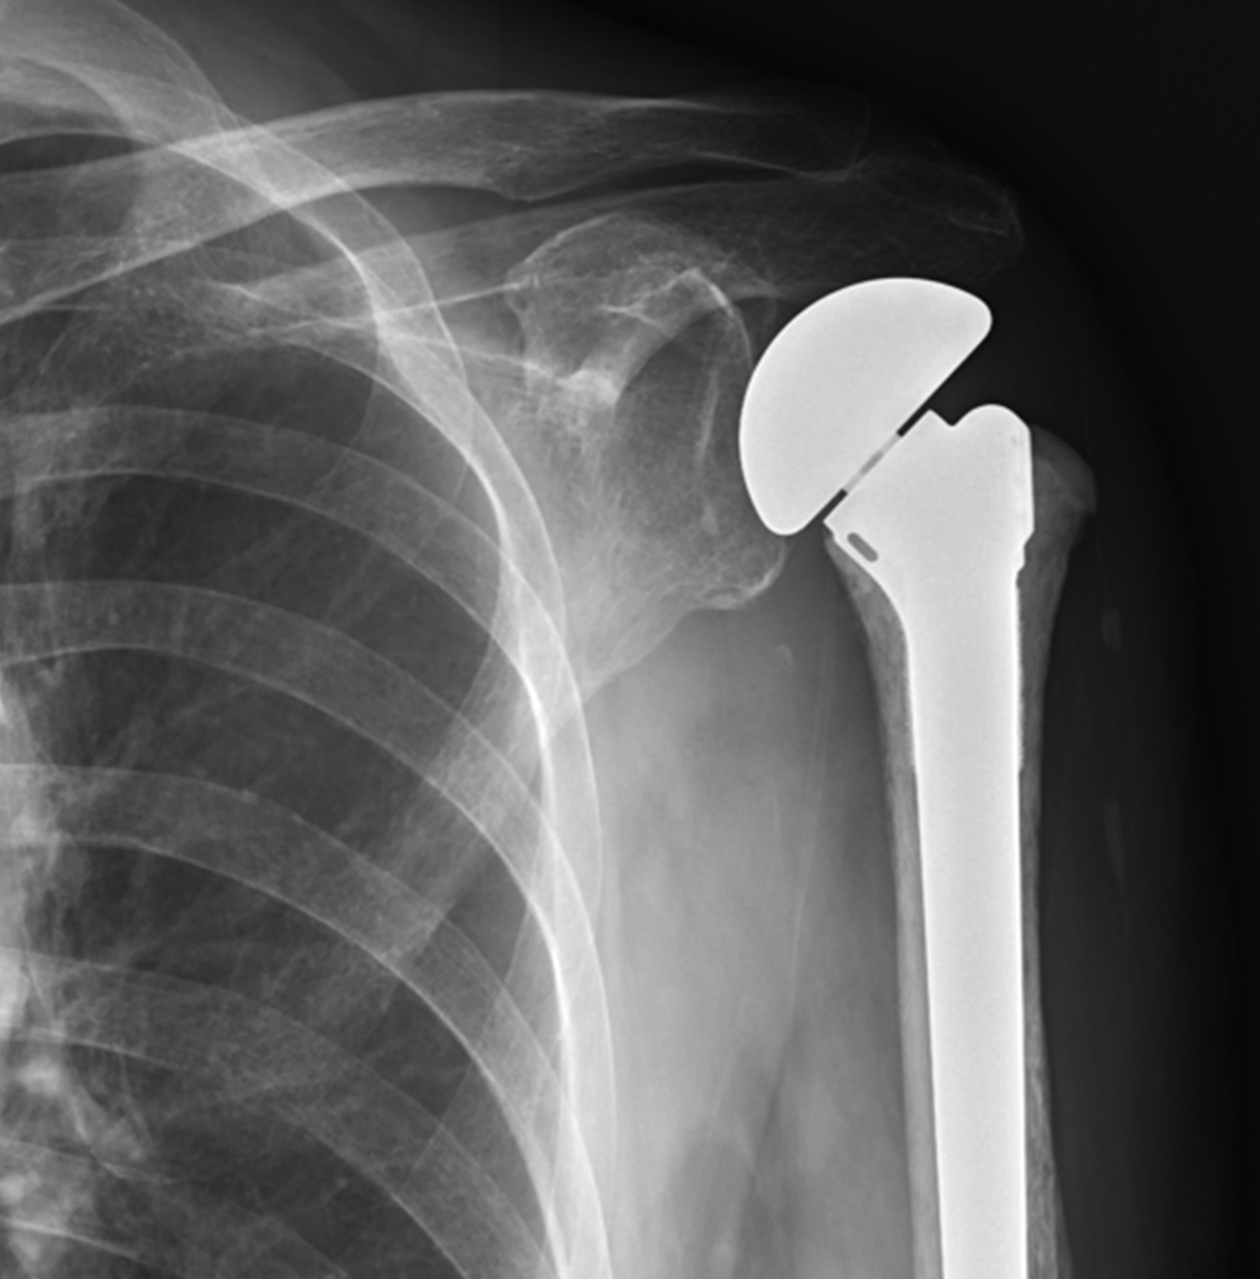

黃先生52歲,左肩疼痛多年,手無法上舉,一年來症狀加劇,經檢查發現肱骨頭缺血性壞死併肩關節炎,核磁共振發現大片全層旋轉肌破裂,接受了反置式人工全肩關節置換手術治療,並投入計劃性復健治療,目前疼痛消失,手已可上舉接近150度。

左側肱骨頭缺血性壞死續發關節炎併旋轉肌腱斷裂,經反置式人工全肩關節置換手術治療。